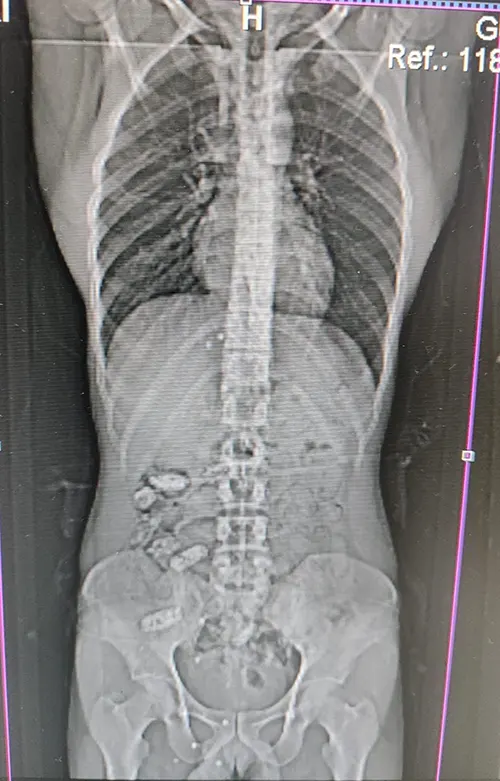

Uyuşturucu kuryesi olduğu ve yutma suretiyle uyuşturucu taşıdığından şüphelenilen şahsın Gümüşhane Devlet Hastanesi’nde yapılan kontrollerinde, midesinde 18 adet kapsül olduğu tespit edildi. Hastanede yapılan müdahalenin ardından şahsın midesinden çıkarılan kapsüllerin içerisinde toplamda 152,29 gram metamfetamin ele geçirildi.